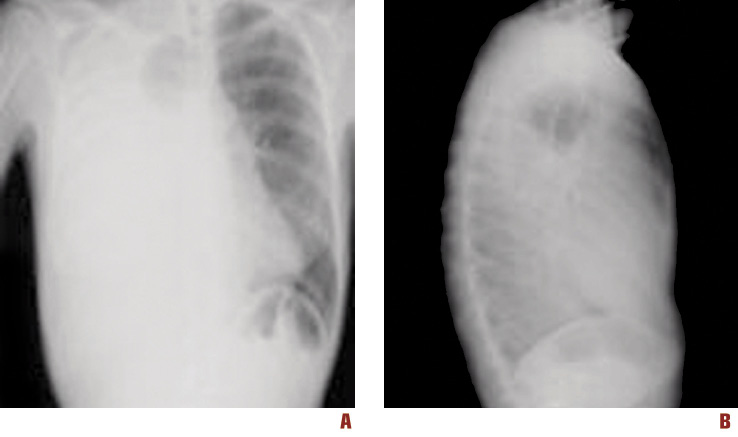

Chest x-ray (Figure 1) showed a massive right pleural effusion.

Figure 1. Chest x-ray of the patient showing a massive right pleural effusion. Frontal (A) and lateral (B) views